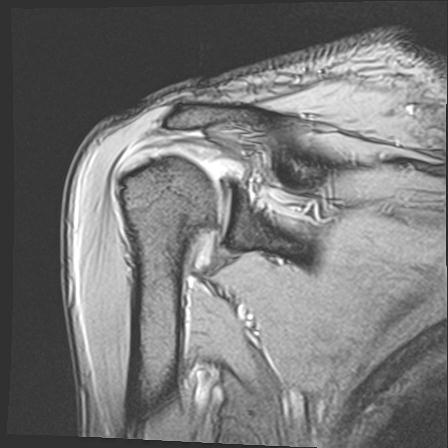

60058 3/9 11/4 右肩 2R+MRI 73歳男性 肩腱板損傷